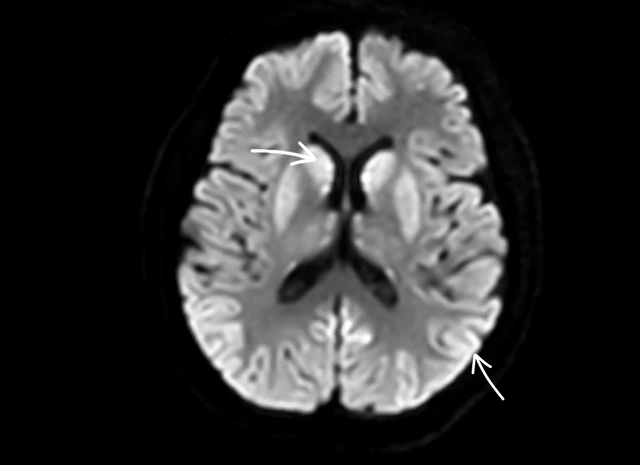

Não bệnh nhân bị tổn thương nặng, rất khó có thể hồi phục. Ảnh: BVCC.

ThS.BS Nguyễn Tiến Đạt cũng cho biết trường hợp bệnh nhân nêu trên do bị ngừng tuần hoàn với thời gian khá lâu, khiến não bị thiếu oxy, bị tổn thương nặng. Tiên lượng bệnh nhân rất khó có thể hồi phục, sẽ tiếp tục hôn mê, thời gian về sau chỉ có thể nằm 1 chỗ.